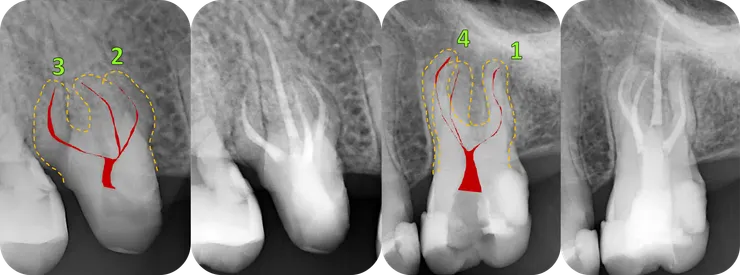

總結這兩顆牙較具挑戰的四個 canals, 單看個別的 canal 彎曲情形,我給它們的難度排名如圖中的綠色編號。DB orifice 上方也是類似的情況,有一區蓋過來的 dentin. 但因為 DB 洞明顯的比 MB2 洞大多了,所以我沒多加處理。就這樣試著把 file 督進去......

因為我覺得,就算 NiTi rotary 再怎麼軟,因為越上端處 file 越粗 (任何 taper 大於 .04 的系統),過彎能力就會越差,風險越高!

因此若是 canal 的第一個彎越大,以及過彎之後底下的 canal 越長,就越困難。

然而為何看起來比較困難的

第一名 26 DB (24mm, PTG F1)

做起來卻感覺比

第二名的 16 MB2 (16.5mm, PTG F1)

輕鬆許多呢?

我覺得可能的原因有三:

1. 16 MB2 比較鈣 (畢竟年紀比較大)

2. 16 MB2 實際上比較彎 (在 PA 看不到的 B-P curve)

3. 經過短短六個月,我快速進步了!哈哈哈!